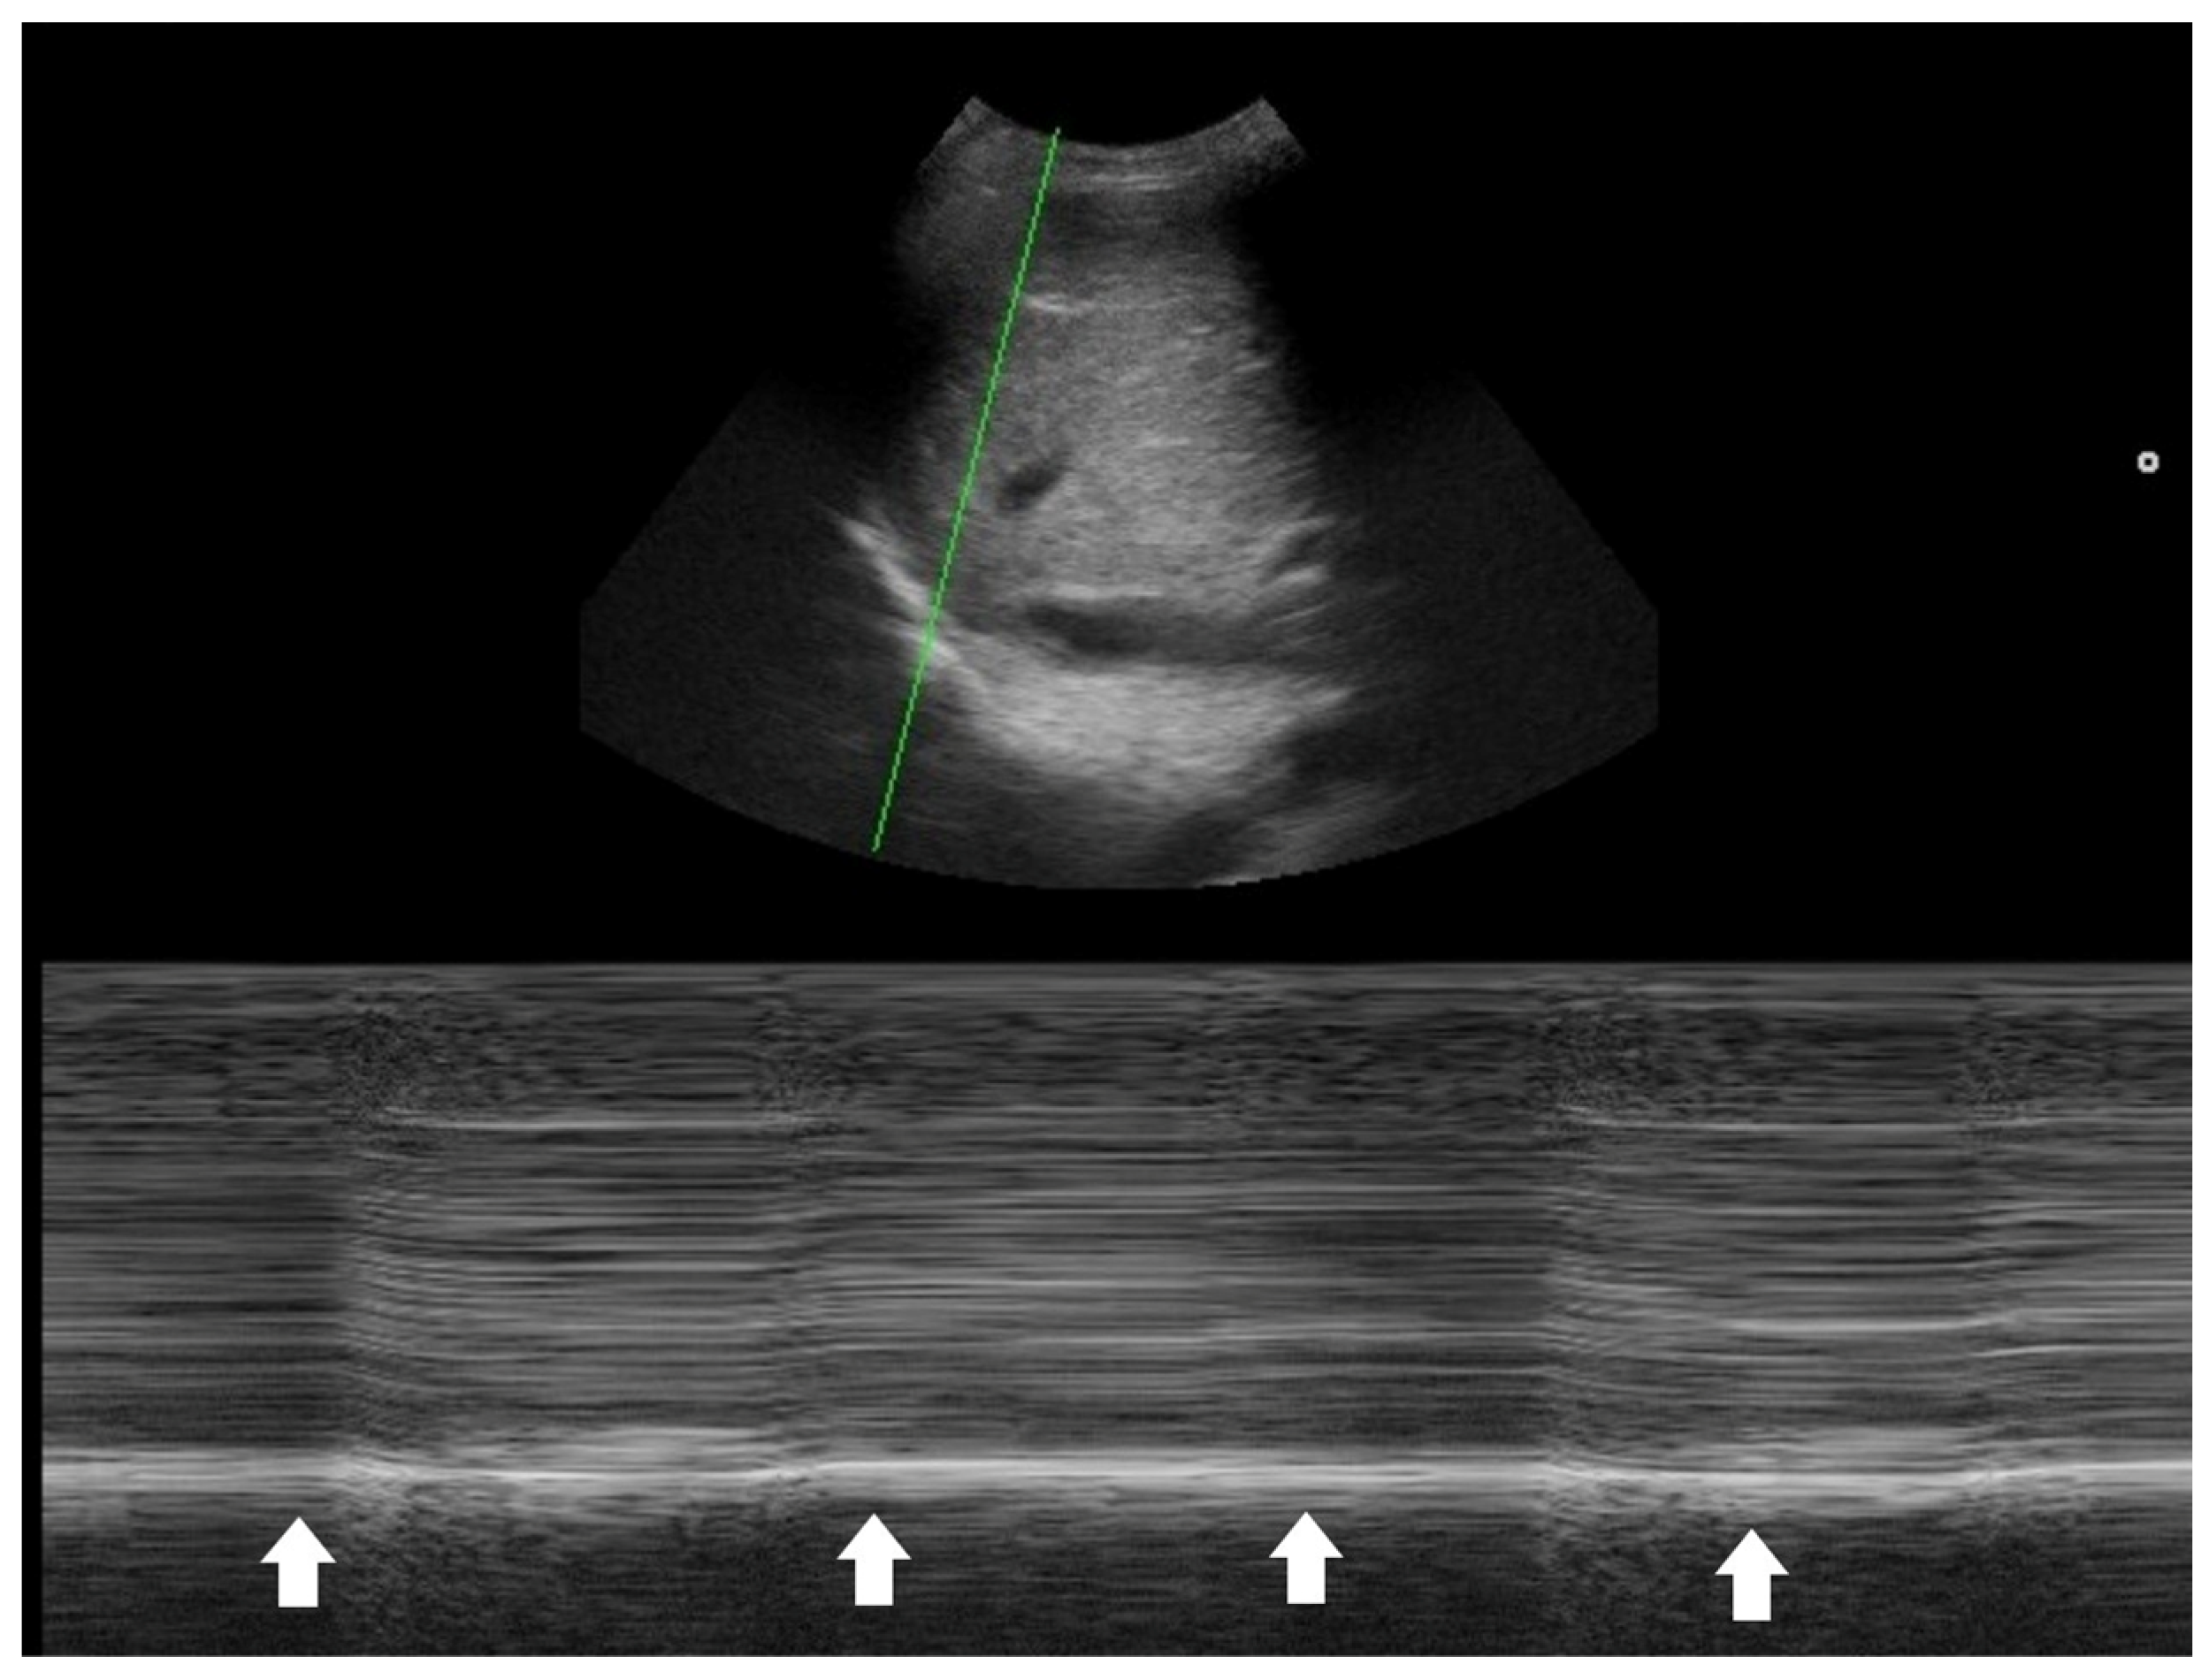

| Suboptimal diaphragm excursion | Poor respiratory strength or endurance |